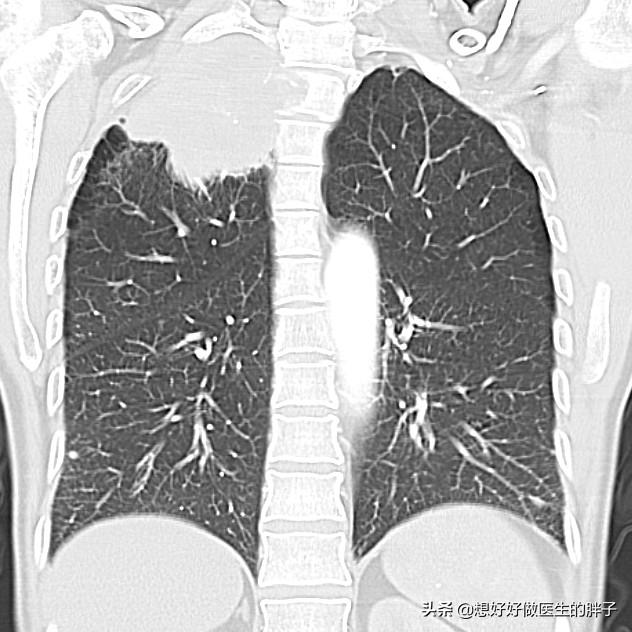

●Lungenkrankheiten.. Es ist relativ selten, dass eine Lungenerkrankung die Entwicklung von Schulter- und Rückenschmerzen verursacht, aber es gibt eine Art von Lungenkrebs namensapikaler LungenkrebsIm Frühstadium verursacht der Tumor keine spezifischen Symptome, aber wenn er wächst, dringt er langsam in das Brustfell ein und kann Schmerzen im hinteren Teil der Schulter verursachen.

Wenn ein solcher Verdacht besteht, ist es wichtig, Folgendes durchzuführenCT-Untersuchung der Lungeum zu klären, ob es einen Platzhalter gibt.